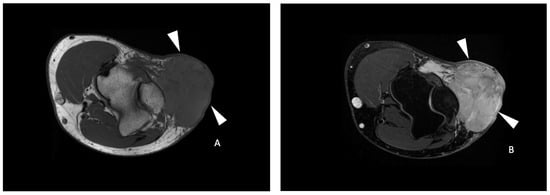

On ADC functional maps, the reader placed a free-form elliptical region of interest (ROI) on the solid tumor area that presented the lowest ADC value, based on the study of Bonarelli et al. []. The mean ADC value of the pixels in this ROI was considered to represent the minimal ADC of the tumor. The mean ADC value of skeletal muscle was obtained by placing another free-form elliptical ROI on normal-appearing muscle adjacent to the tumors evaluated of similar size (Figure 1). The tumor ADC ratio was calculated by dividing minimal tumor ADC by muscle ADC values.

Figure 1.

Functional imaging post-processing and analysis in a 69-year-old male with a leiomyosarcoma of the left popliteal fossa. Sagittal T2-weighted fat-saturated (A) and axial T1-weighted contrast-enhanced (B) MR images showing an ovoid mass (white arrowheads) with a heterogeneous hyperintense T2 signal and enhancement of the posterior compartment of the thigh in the popliteal fossa. (C) DCE (dynamic contrast-enhanced) AUC (area-under-the-curve) functional map in the axial plane showing a homogeneously enhancing tumor (arrowheads). Two free-form ROIs were placed. One on the area of highest tumor enhancement (green line) and another of the corresponding size in the muscle (white line). (D) Axial ADC (Apparent Diffusion Coefficient) functional map showing the same tumor (arrowheads). (E) An axial ADC functional map with an ROI of the corresponding size was drawn in the muscle (black line).

DCE AUC functional maps were evaluated, and the reader placed a free-form elliptical ROI on the tumor area most intensively enhancing and on a nearby artery. A second ROI of the corresponding size was placed on adjacent normal-appearing striated muscle. Tumor-to-muscle ratios were obtained by dividing tumor AUC by muscle AUC values.